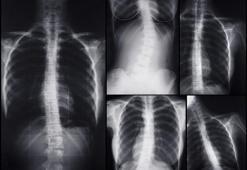

Omurgada görülen eğrilikler olarak tanımlanan skolyozun, erken teşhis edilmediğinde ciddi sağlık sorunlarına neden olduğunu belirten Ortopedi ve Travmatoloji Uzmanı Prof. Dr. Mustafa Özdemir, “Erken teşhis edilen vakalarda tedavi seçenekleri çok daha geniştir ve cerrahi müdahale gereksiz yere gündeme gelmeyebilir. Skolyozda tedaviye yönelik birçok seçenek mevcuttur ve hastalarımız bu seçeneklerle oldukça başarılı sonuçlar elde edebilirler” dedi.

Çocuklarda, özellikle hızlı büyüme dönemlerinde omurgada eğrilikler yaşanabiliyor. Bu dönemlerde çocukların omuzları arasındaki dengesizlik, kürek kemikleri ve karın bölgesindeki asimetriler skolyozun ilk belirtileri olabiliyor. Zayıf çocuklarda skolyoz daha rahat fark edilebilirken kilolu çocuklarda bu belirtiler gözden kaçabiliyor. Aşırı kilolu çocuklarda karın bölgesinde kilodan kaynaklanan boğumlar arasında asimetri olup olmadığının kontrol edilmesi skolyoz ile ilgili anne babalara fikir verebiliyor. Skolyozun tedavisinde eğriliğin derecesi ve yaş önemli bir faktör oluştururken sporla ilgilenen çocuklarda ipli skolyoz ameliyatı ön plana çıkıyor.

Skolyozun kız çocuklarında erkeklere göre 4 kat daha fazla görüldüğüne değinen uzmanlar, "ilk tanıda yaş ne kadar küçük ve eğrilik ne kadar büyükse ilerleme ihtimali o kadar büyüktür. Bu eğrilikler daha çok ergenlikten önce başlar ve ilerleyicidir. Hastanın ergenlikten sonra iskelet sisteminin olgunlaşmasıyla birlikte ilerlemesi durur” diyor.

Skolyozun görülme sıklığının kadınlarda erkeklere oranla 10 kat daha fazla olduğunu dile getiren Fizik Tedavi ve Rehabilitasyon Uzmanı Prof. Dr. Yüksel Ersoy, “Skolyoz, omurga eğriliğinin genel ismidir. Bu eğrilik S tipinde veya C tipinde görülebilirken, omurganın dönüş hareketleriyle de meydana gelmiş olabilir. Bu iki durum birlikte de olabilir. Bu eğrilikler genel olarak belde ve sırtta meydana geliyor. İlgili bölgelerde asimetriye ve normalden farklı görünüme sebep olabiliyor” dedi.